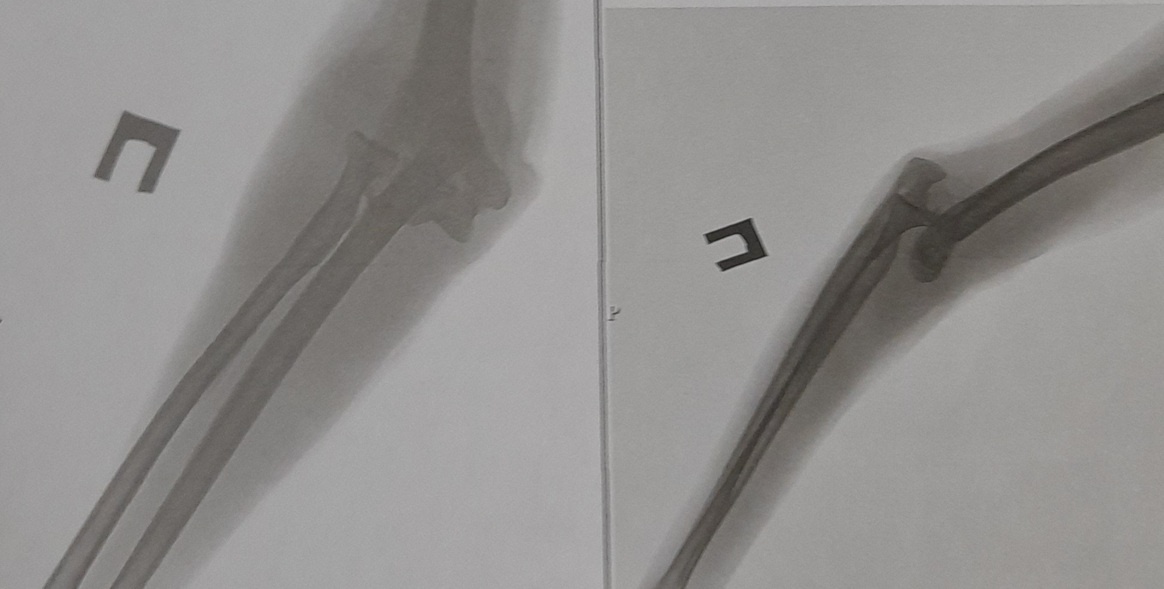

Если кому интересно, куда я пропала, и когда вернусь, вот вам пара картинок, которые все объяснят без слов.

С того злополучного утра прошло уже почти два месяца. Много могла бы рассказать про нашу отечественную медицину... Особенно запомнилось, как меня за сутки трижды отправляли на рентген, а на вопрос - не многовато ли? - беспечно ответили: "Ну вам же не рожать".